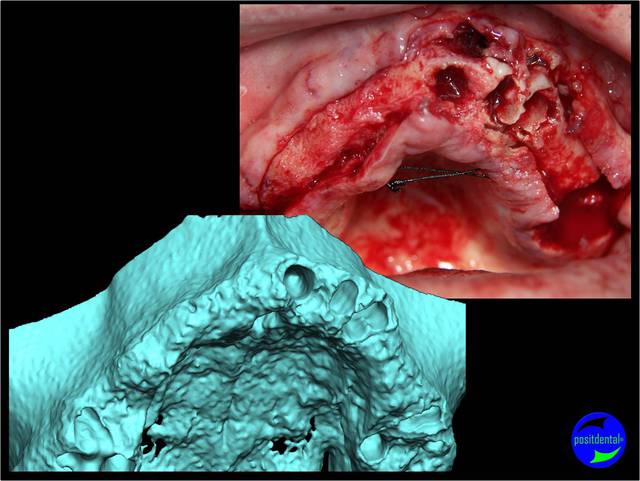

planif cas 1

Si tu as suivi les cas présentés depuis plusieurs années les bridges provisoires ont une armature métal pour la rigidité du fixateur externe, l’intervention se déroule en 1 seul temps chirurgical donc sans prise d’empreinte, c’est pour cela que je parle de MCI. Pour la passivité du bridge avec le système Nobel Guide et leurs piliers expansifs je n’ai vue aucun cas clinique présenté sur le forum. As-tu déjà utilisé le procédé ? Dans les cas présentés sur la vidéo, aucune clé de positionnement n’a été utilisée, le placement des piliers se fait selon la simulation implantaire assistée par ordinateur, leurs présentations a été faite en prospective par OTP, modèle 3D et à la demande de beotien la solution pilier fixe a été retenu à la place du bridge transvisé. Quel sont les compléments d’information que tu as besoin et ou la photo ne te suffi pas ? Pour le protocole d’une MCI, empreintes des maxillaires, dimension verticale de l’occlusion, définition de l’esthétique souhaitée, prescriptions, réalisation du Positscan, traitement des informations à partir des données DICOM, simulation implantaire assistée par ordinateur, validation, réception des DMSM selon les types d’implants et encastillages les procédures varient. Quel système implantaire utilise-tu ?

Dans le protocole Positdental de MCI l’armature métal contraint les implants à conserver la position initiale de leurs poses et si un bridge provisoire induit des forces sur les implants c’est qu’il ne respecte pas celle-ci. Pendant la mastication la rigidité du provisoire assure une répartition des contraintes sur l’ensemble des implants.

Je viens de revoir au cabinet un des 3 cas, car la céramique de la 25 était fracturée.

J'ai pris une photo (iphone) avec le bridge déposé avant de mettre temporairement le bridge coping de Posit. Pas la peine de commenter le bas je n'en suis pas responsable.